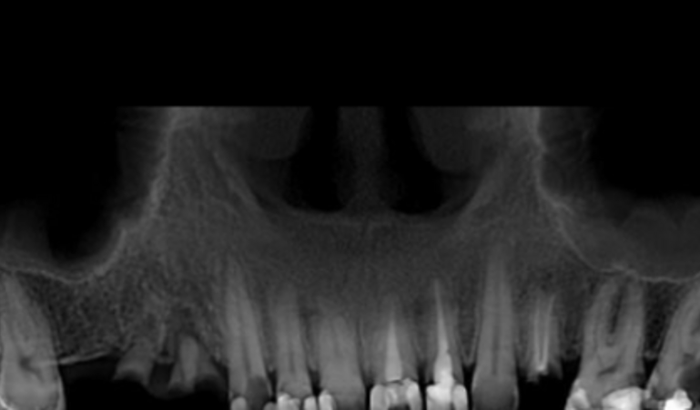

Oi, pessoal. Estou passando por um momento muito difícil e preciso compartilhar com vocês uma situação de saúde que exige muita urgência. Descobri que preciso realizar duas cirurgias odontológicas o mais rápido possível, onde terei que retirar todos os meus dentes e colocar pinos e próteses. O motivo é grave: tenho uma bactéria no osso, que está necrosando e colocando minha saúde em risco.